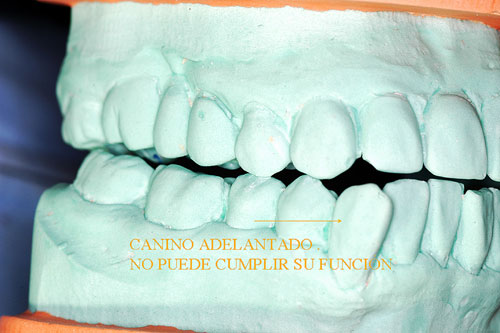

En ellos podemos observar múltiples detalles que son difíciles de ver en boca. Podemos ver biotipos, alineación tridimensional, pérdidas de sustancias, etc. Pero sobre todo en los modelos ya montados en ORC (Oclusión en Relación Céntrica), podremos observar las Discrepancias de oclusión entre lo que habitualmente hace el paciente con su mordida y la situación posicional de su ATM, que puede o no coincidir con lo fisiológico y estructural.

En este caso observamos que estando su ATM en Relación Céntrica, al cerrar la boca, solo un punto contacta del lado derecho del enfermo Punto Prematuro de Contacto), lo que hace imposible que con ese único punto desarrolle su función masticatoria y se vea obligado a mover su mandíbula hacia una posición de conveniencia, donde sean muchos más los puntos contactantes que mejoren el desgarro y aplastamiento de los alimentos.

En O.R.C. el Canino no funciona

Disclusión Correcta Canino/Premolar